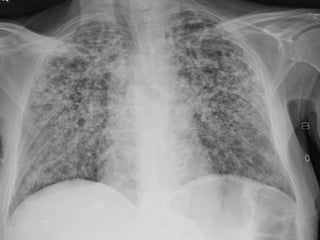

Introduction

• Acute respiratory illness

• Either segmental or affecting more than one lobe

• Pneumonia defined as inflammation with

exudative solidification of the lung parenchyma.

• Lung parenchyma is the portion of

the lung involved in gas transfer - the alveoli,

alveolar ducts and respiratory bronchioles.

Investigation

• Radiological examination

Radiological examination

• Chest x-ray: An x-ray exam will allow your doctor to

see your lungs, heart and blood vessels to help

determine if you have pneumonia

• CT of the lungs: A CT scan of the chest may be done

to see finer details within the lungs and detect

pneumonia that may be more difficult to see on a

plain x-ray.